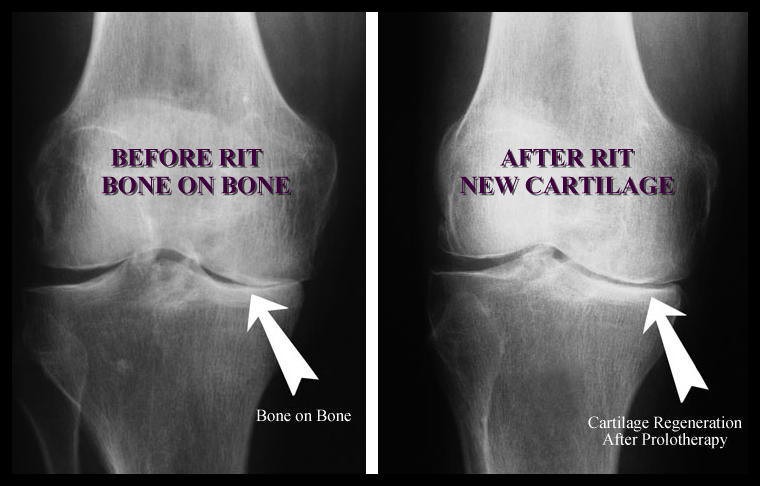

Knee X-rays - Before and After

Prolotherapy is part of the comprehensive approach we take to curing chronic pain. We evaluate each patient thoroughly with a personal history and physical exam and specialized laboratory analysis. We may ask patients to have X-rays performed before receiving prolotherapy. In all cases involving chronic pain, Dr. Hoffmann will use his expertise in dietary and nutritional medicine and recommend specific supplements to maximize your health and ability to heal.